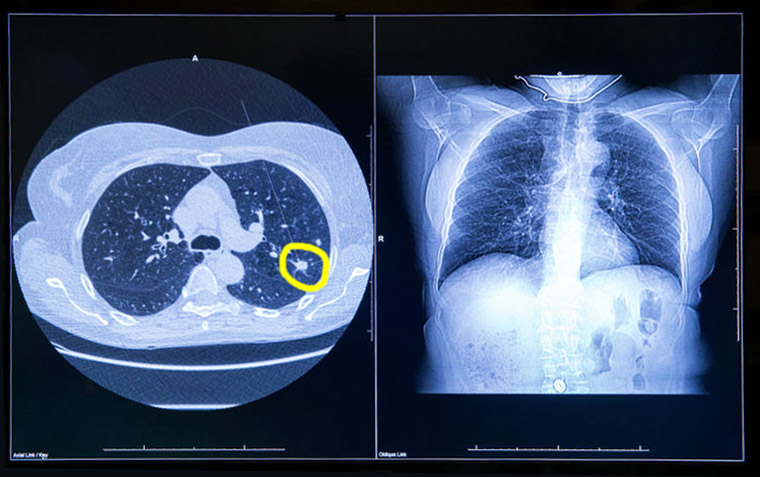

Sobrediagnóstico en el rastreo de cáncer de pulmón

En el estudio danés de tomografía computada de baja dosis para el cribado de cáncer de pulmón se halló que 2 de cada 3 casos detectados podrían corrresponder a sobrediagnóstico. JAMA Internal Medicine, 13 de agosto de 2018

Resultados de la implementación del tamizaje para cáncer de pulmón

La experiencia del rastreo de cáncer de pulmón con tomografía de baja dosis en hospitales de la Administración de Veteranos muestra una tasa elevada de falsos positivos que genera un enorme esfuerzo organizacional. JAMA Internal Medicine, 30 de enero de 2017